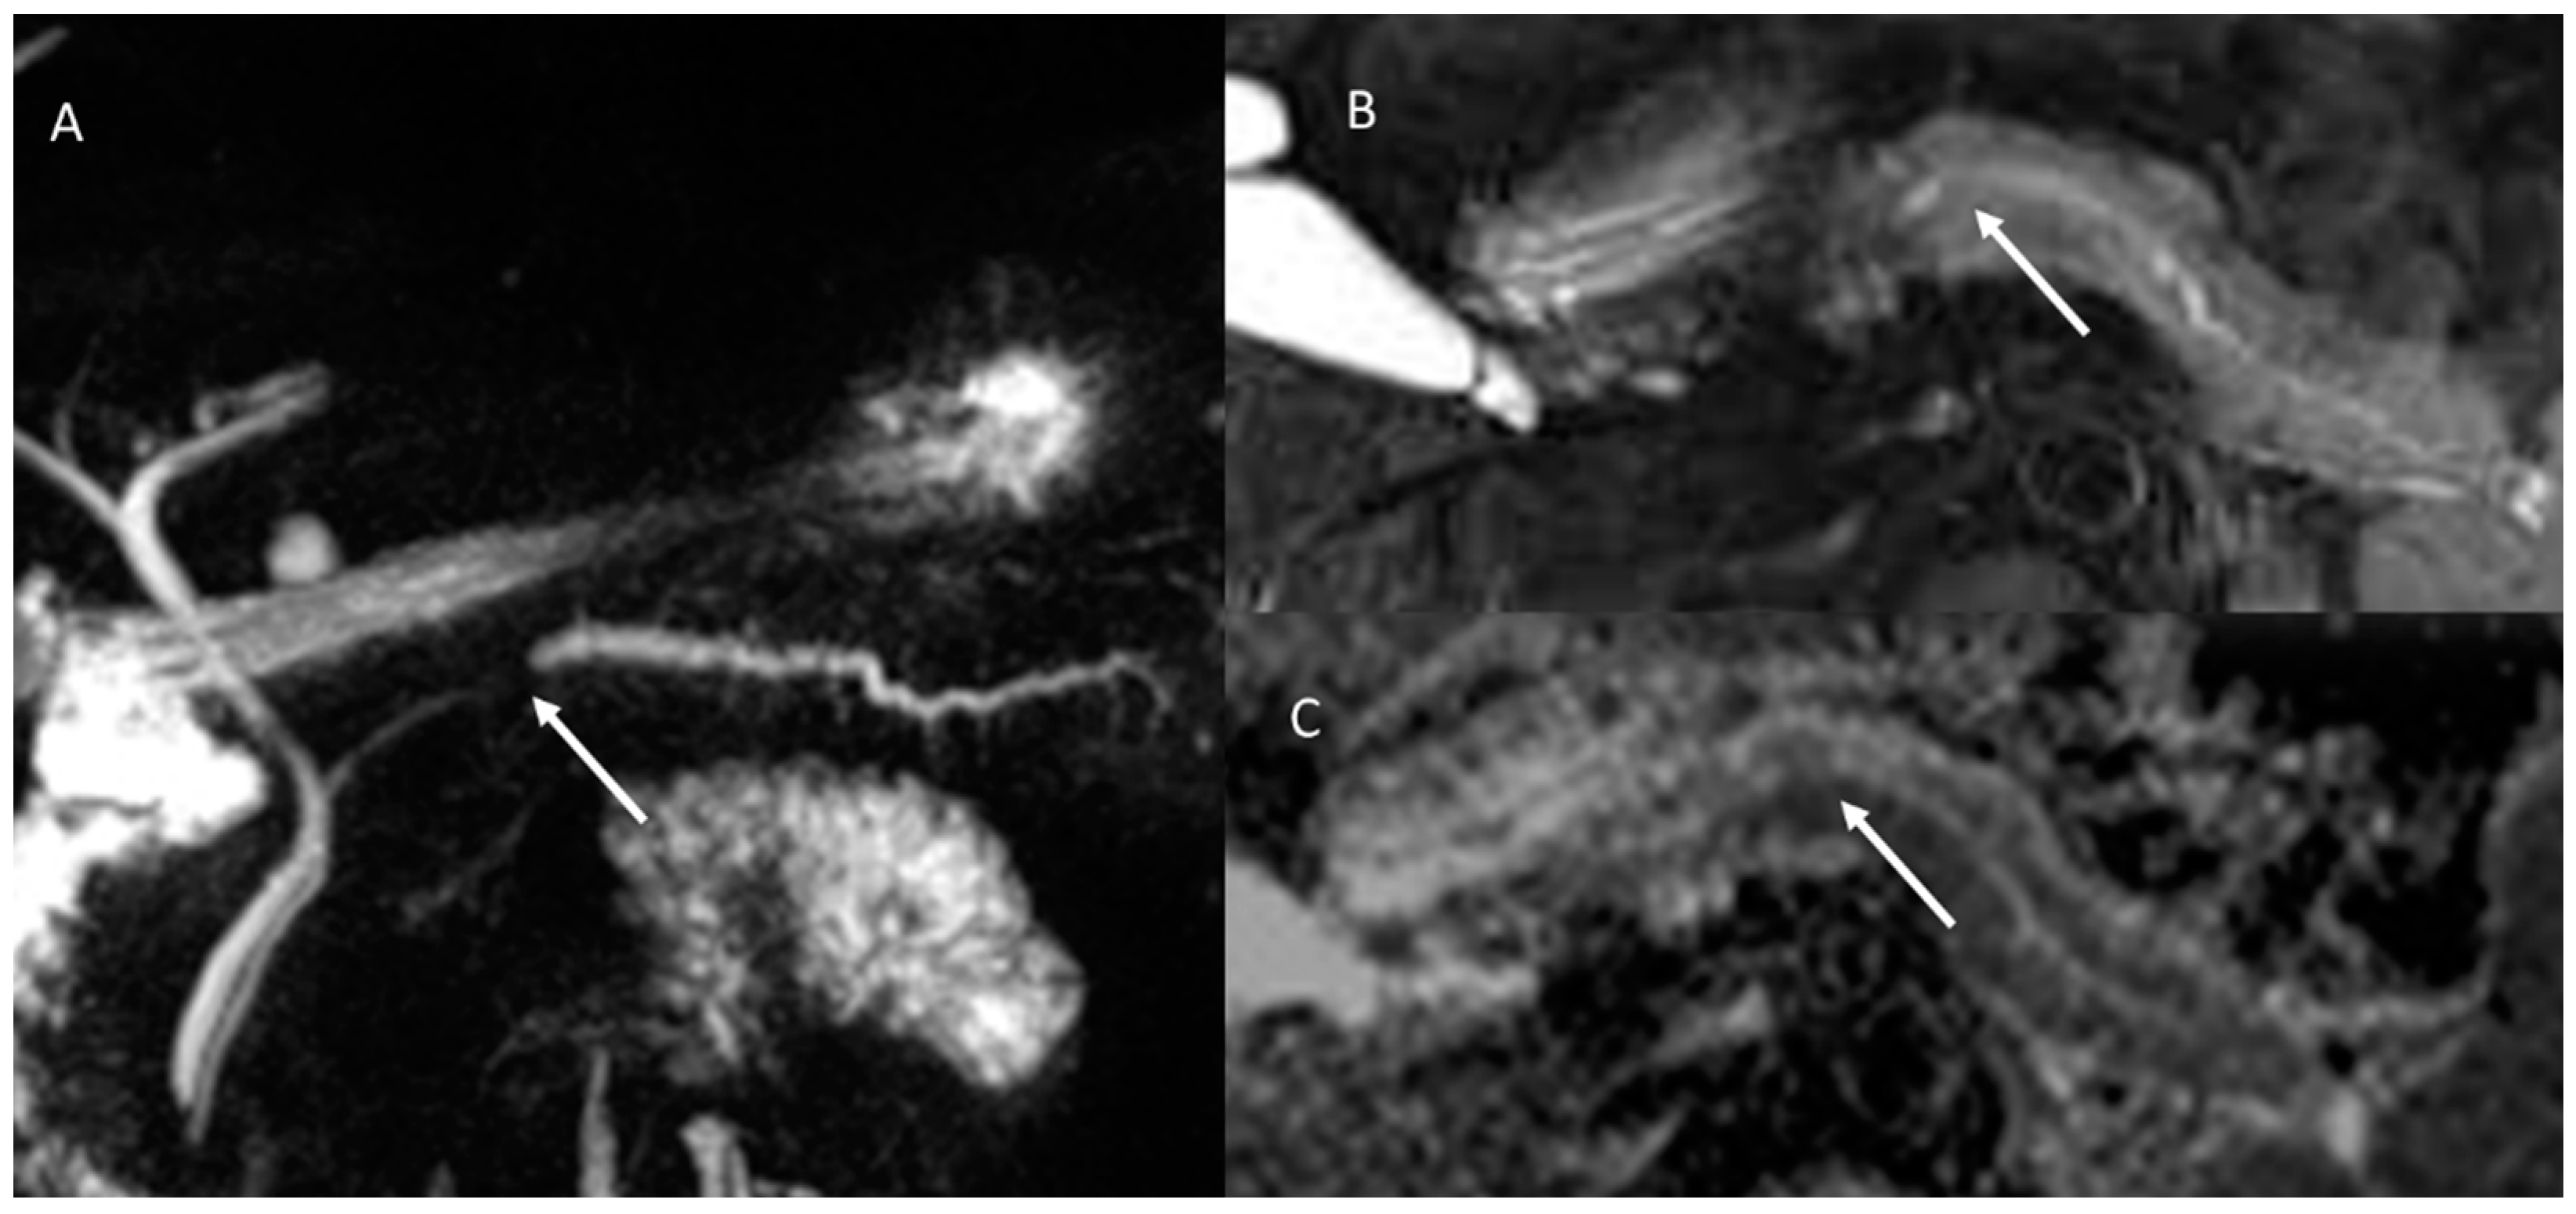

- Granata, V.; Grassi, R.; Fusco, R.; Galdiero, R.; Setola, S.V.; Palaia, R.; Belli, A.; Silvestro, L.; Cozzi, D.; Brunese, L.; et al. Pancreatic cancer detection and characterization: State of the art and radiomics. Eur. Rev. Med. Pharmacol. Sci. 2021, 25, 3684–3699. [Google Scholar] [CrossRef] [PubMed]